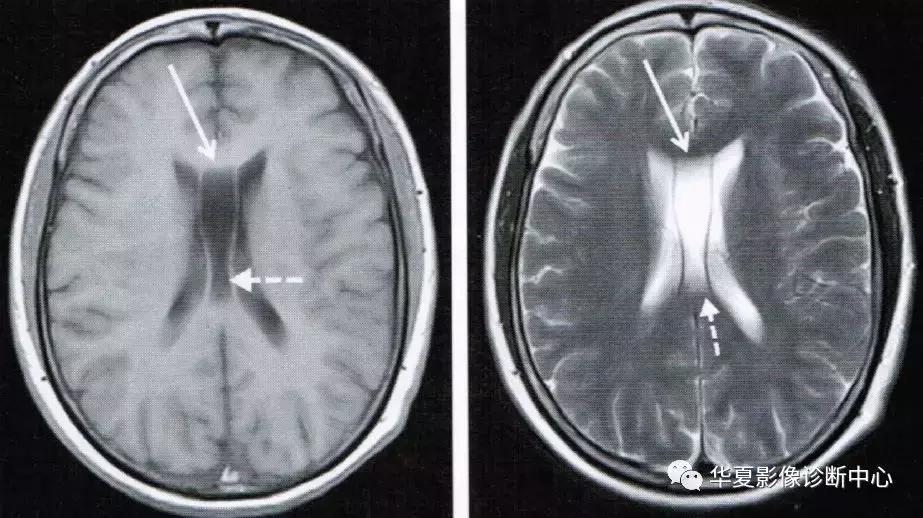

上图为第五脑室(实箭头)、第六脑室(虚箭头)

Vergae腔位于胼胝体和后穹隆之间,上部和后部是胼胝体的体部与压部,前方和侧方是穹隆柱和体部,下方是穹隆联合,向后下延伸终止于穹隆脚附近。一般认为Vergae腔多为透明隔间腔向后扩展形成,但偶尔也可单独存在,形成原因可能是海马联合闭合不全。临床上Vergae腔常与透明隔间腔同时存在,并且互通,故统称为第五、六脑室;Vergae腔与脑室系统一般不相通。